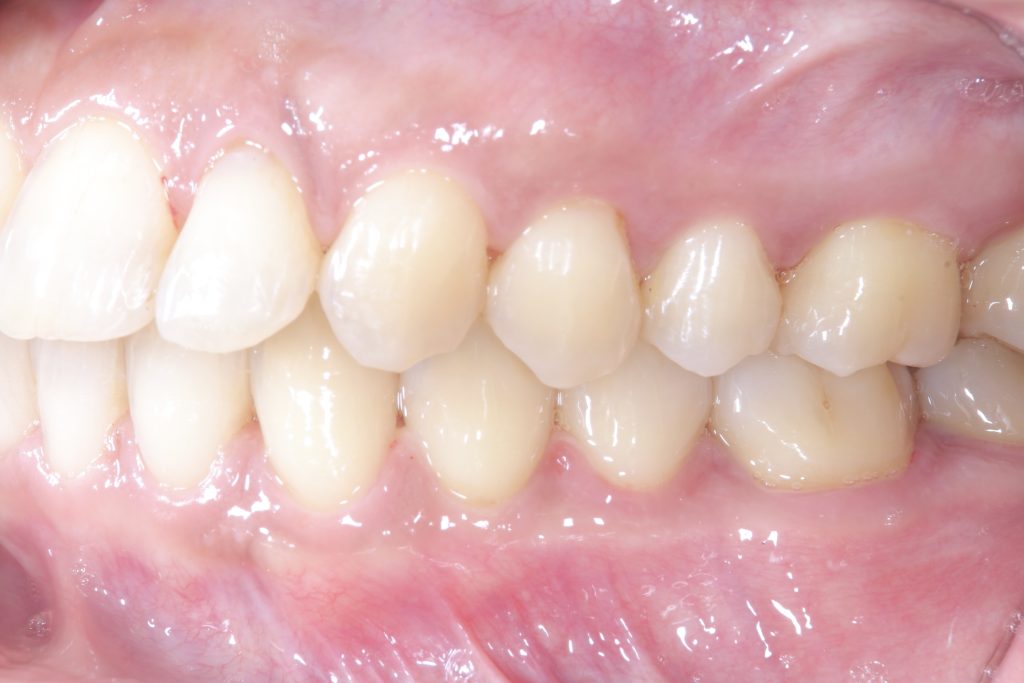

受け口の状態により、上の歯が内側に入り込み、反対の噛み合わせになっている部分が見られました。見た目の問題だけでなく、噛み合わせのバランスにも影響を与えていました。

- 前歯部交叉咬合を伴う不正咬合

- ゴムメタルワイヤー矯正

- 2024年9月6日(10ヶ月)